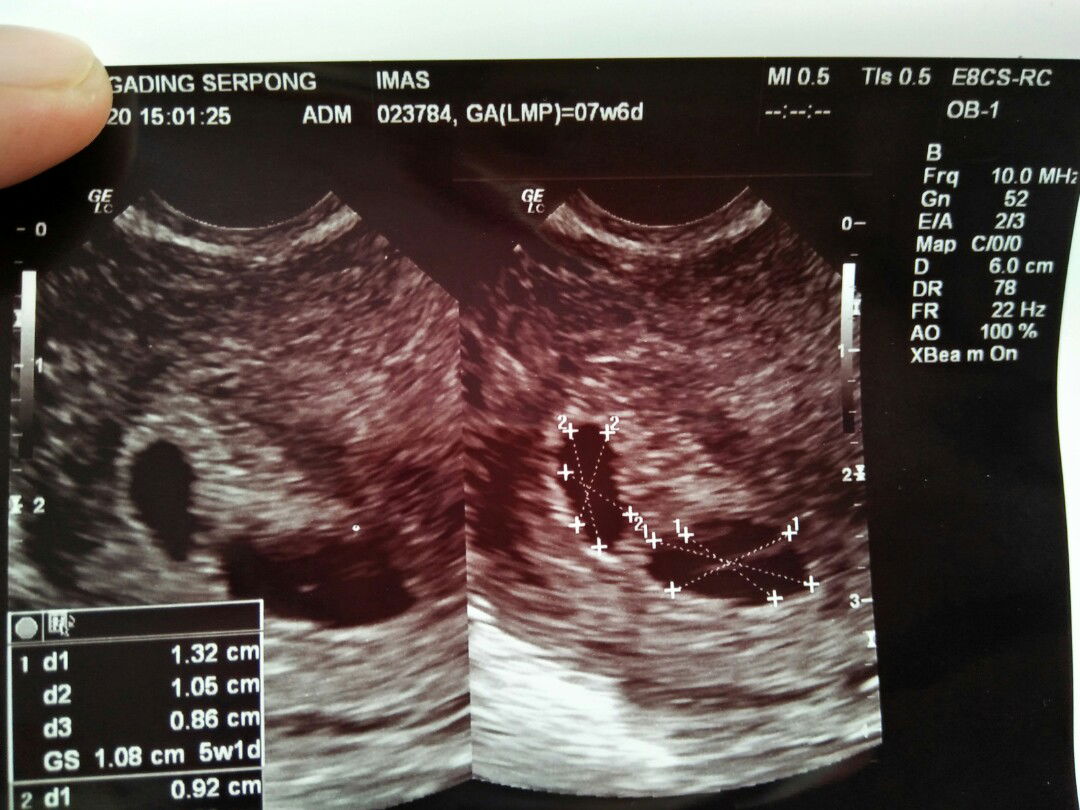

Kemungkinan punya baby kembar doain bunda biar sehat semuanya amiiin